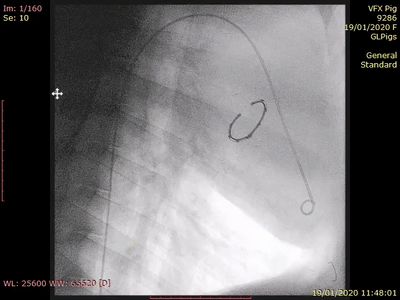

VALFIX是通過經(jīng)房間隔入路到達(dá)二尖瓣環(huán),將開放式心臟瓣膜手術(shù)轉(zhuǎn)變?yōu)榻?jīng)導(dǎo)管手術(shù)。先是通過自膨脹系統(tǒng)將多根縫線固定在瓣環(huán)上,然后收回自膨脹系統(tǒng),再將瓣環(huán)輸送到二尖瓣瓣環(huán)上方,最后VALFIX瓣環(huán)通過縫線縫合到二尖瓣環(huán)上,從而縮小二尖瓣瓣環(huán)并消除返流。

VALFIX動(dòng)物模型植入